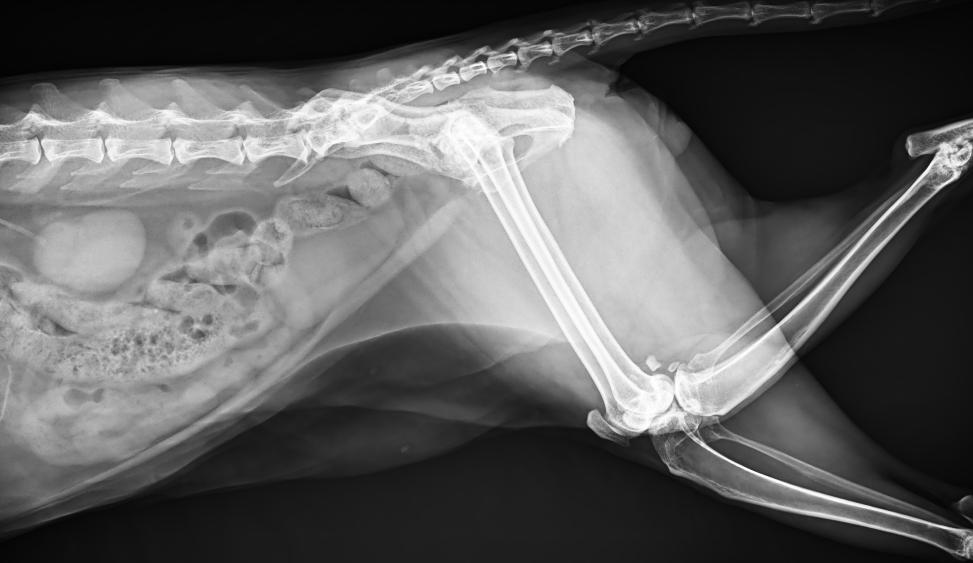

● 進口高品質(zhì)球管,大功率、高熱容量、微焦點,1.0/2.0mm雙焦點設(shè)計

● 25kHz高主逆變頻率,輸出電壓更穩(wěn)定;瞬時定格影像,無拖尾現(xiàn)象